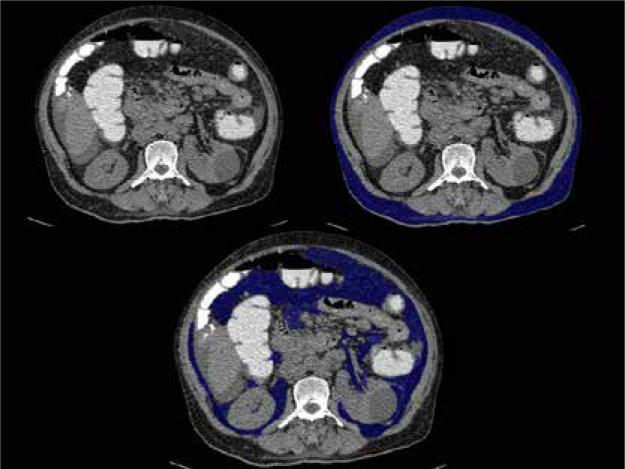

Abdominal obesity plays a significant role in the development of metabolic syndrome, with individual metabolic risk profiles for visceral and subcutaneous adipose tissues. This study aimed to calculate and correlate the subcutaneous, visceral, and total fat compartment volume in metabolic and non-metabolic syndrome patients.

MATERIAL AND METHODS

This was a cross-sectional study conducted on 112 patients categorized into Group A (with metabolic syndrome) and Group B (without metabolic syndrome). They were subjected to computed tomography (CT) study of the abdomen using a 128-slice MDCT scanner. Body mass index (BMI), visceral fat volume (VFV), subcutaneous fat volume (SFV), and total fat volume (TFV) were calculated and correlated with biochemical evidence of metabolic syndrome.

腹部肥胖在代谢综合征的发展中起重要作用,内脏和皮下脂肪组织具有个体代谢风险特征。本研究旨在计算代谢综合征患者和非代谢综合征患者的皮下、内脏和总脂肪腔室体积,并进行相关性分析。

材料与方法

这是一项横断面研究,对112例患者进行了分组,分为A组(患有代谢综合征)和B组(未患有代谢综合征)。使用128层MDCT扫描仪对他们进行腹部计算机断层扫描(CT)研究。计算体重指数(BMI)、内脏脂肪体积(VFV)、皮下脂肪体积(SFV)和总脂肪体积(TFV),并与代谢综合征的生化证据进行相关性分析。